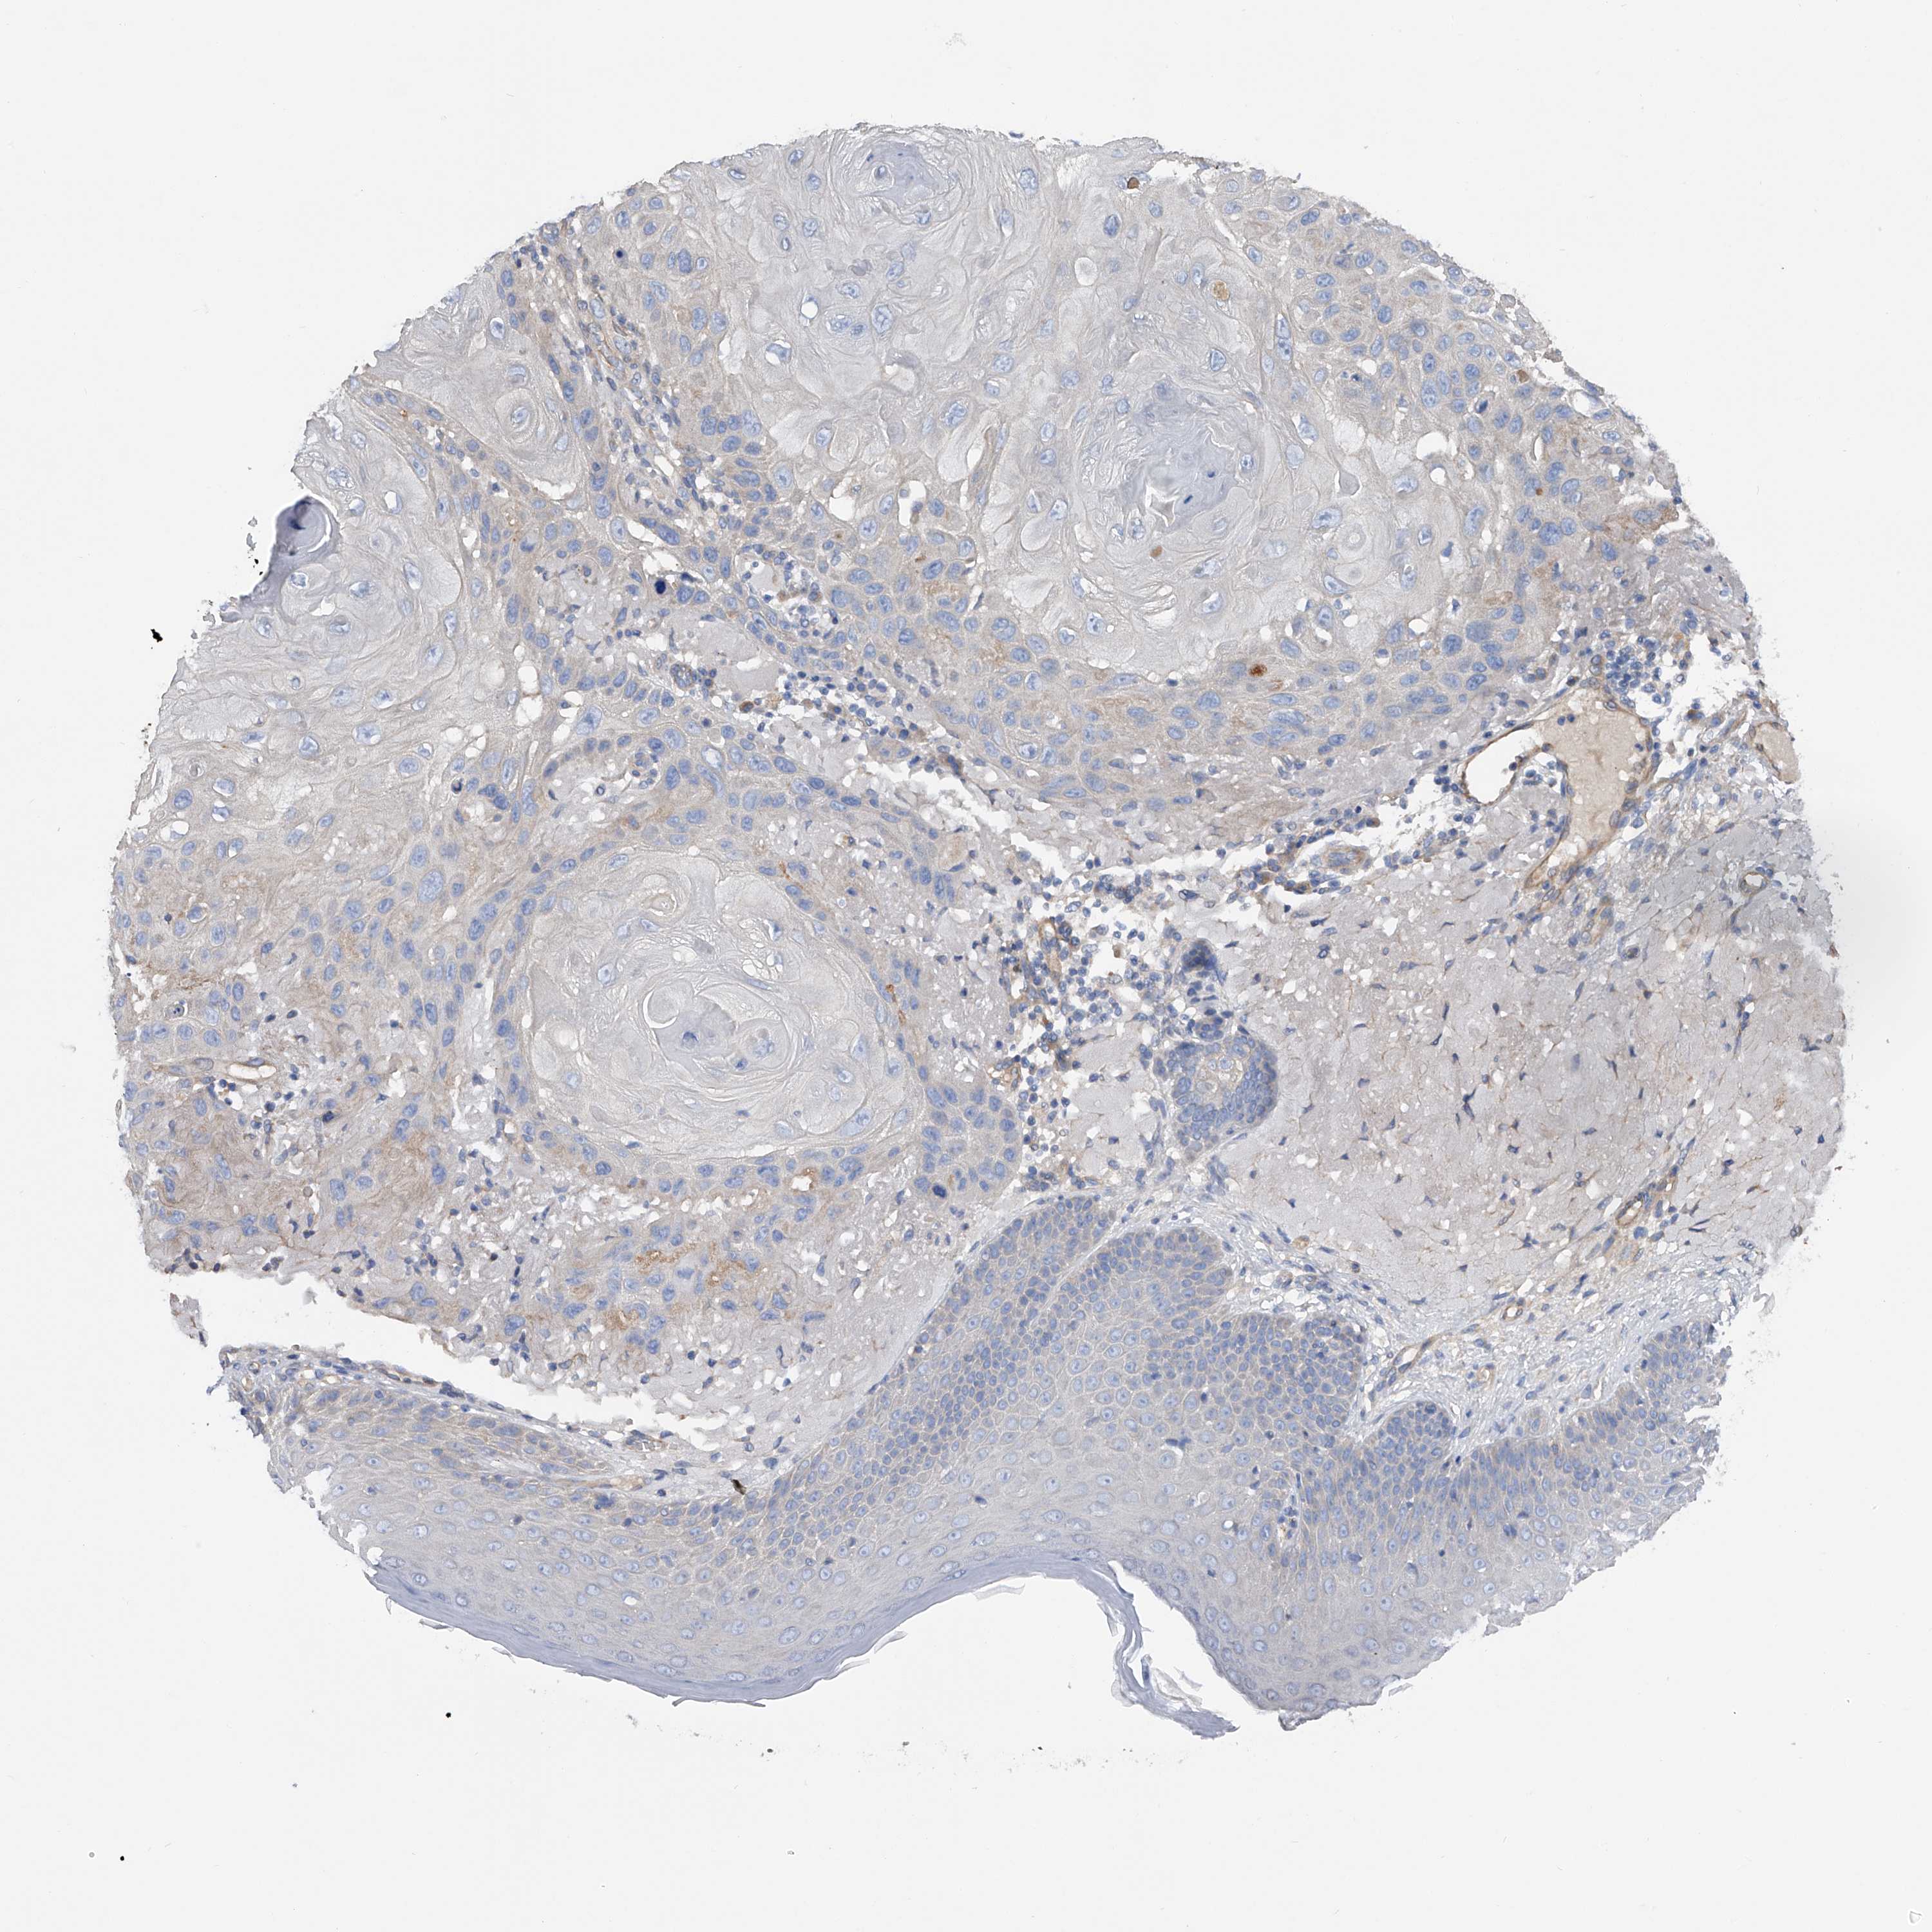

CANCER SKIN CANCER Show tissue menu

Basal cell and squamous cell cancer

SKIN CANCER - Protein expressioni

A mouse-over function shows sample information and annotation data. Click on an image to view it in a full screen mode. Samples can be filtered based on level of antibody staining by selecting one or several of the following categories: high, medium, low and not detected. The assay and annotation is described here.

Each image is clickable and will lead to virtual microscopy that enables deeper exploration of all samples and also displays staining intensity scores, fraction scores and subcellular localization as well as patient and tissue information for each sample.

Antibody HPA030105

Basal cell carcinoma